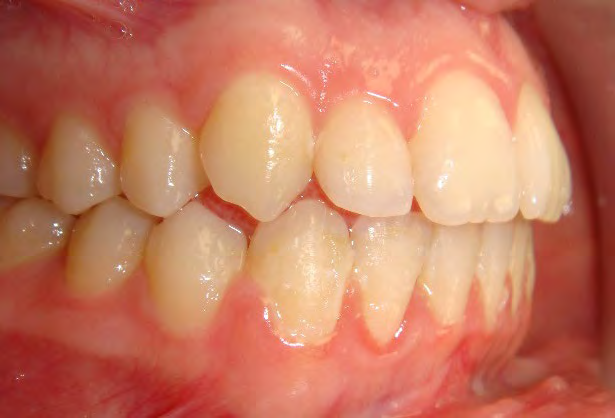

All of the patients below had been told they required extractions by orthodontists, some insisting that they could not be treated without extractions.

They were all treated without extractions, head gear or facemasks at Vakresmil and represent just a small sample of cases treated between 2004–2014.

The patient below had severe crowding of both upper canines and the lower right 5. The upper 4’s and 2’s were actually in contact.